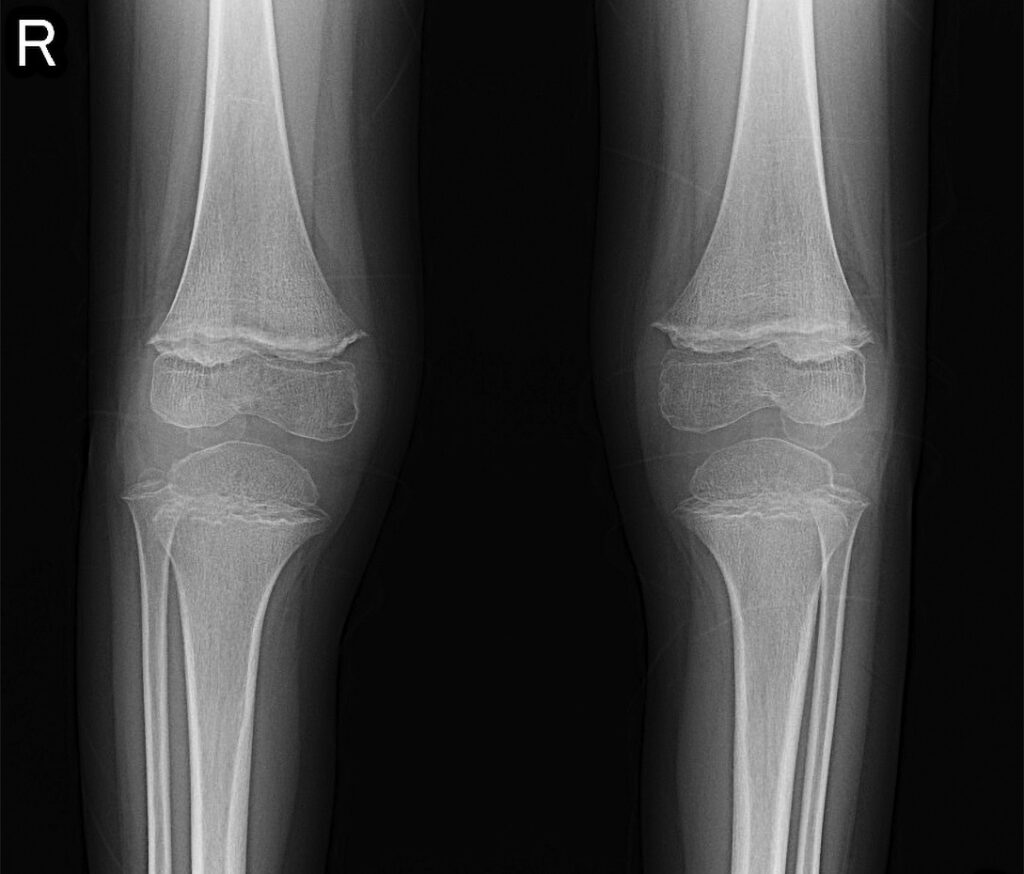

検査所見:手術直前の血液検査結果を表1に、膝関節部の単純X線写真を図3に示す。